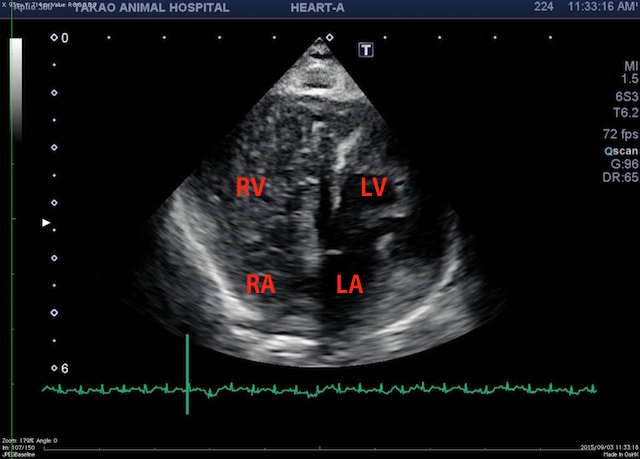

(RV:右心室 RA:右心房 LV:左心室 LA:左心房))

造影超音波検査にて心室中隔の欠損は無かったです。造影剤は静脈から入れていきます。